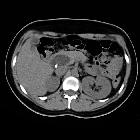

Choledochoceles refer to a specific type of choledochal cyst (type III under the Todani classification system). In this type, there is dilatation of the intramural portion of the distal common bile duct within the duodenal wall. Its precise etiology is not clear . Patients are usually adolescents and may present with a recurrent crisis of right upper quadrant pain, hyperamylasemia, or jaundice.

Malignant transformation of a choledochocele occurs very rarely.

When a choledochocele is small and symptomatic, it may be treated with an endoscopic sphincterotomy. Larger cysts are often removed by a surgical cystoduodenostomy.